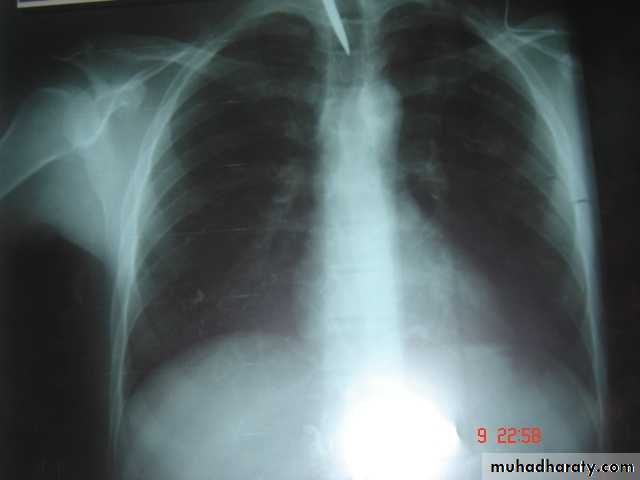

• A-Asymptomatic• Any smooth homogenous opacity of uniform density with clear cut border and little or no reaction around it on a chest X-Ray is a hydatid cyst unless proved the other wise .

• Radiological Findings

• 1-Smooth homogenous opacity (Intact H.C).• 2-Partial rupture (per vesicular pneumocyst).

• 3-Complete rupture (Water –lilly sign) .

• 4-Formation of lung abscess(Air –fluid level) .

• 5-Completely coughed out cyst(empty cavity )

• 6-Rupture into the pleura (hydropneumothorax)